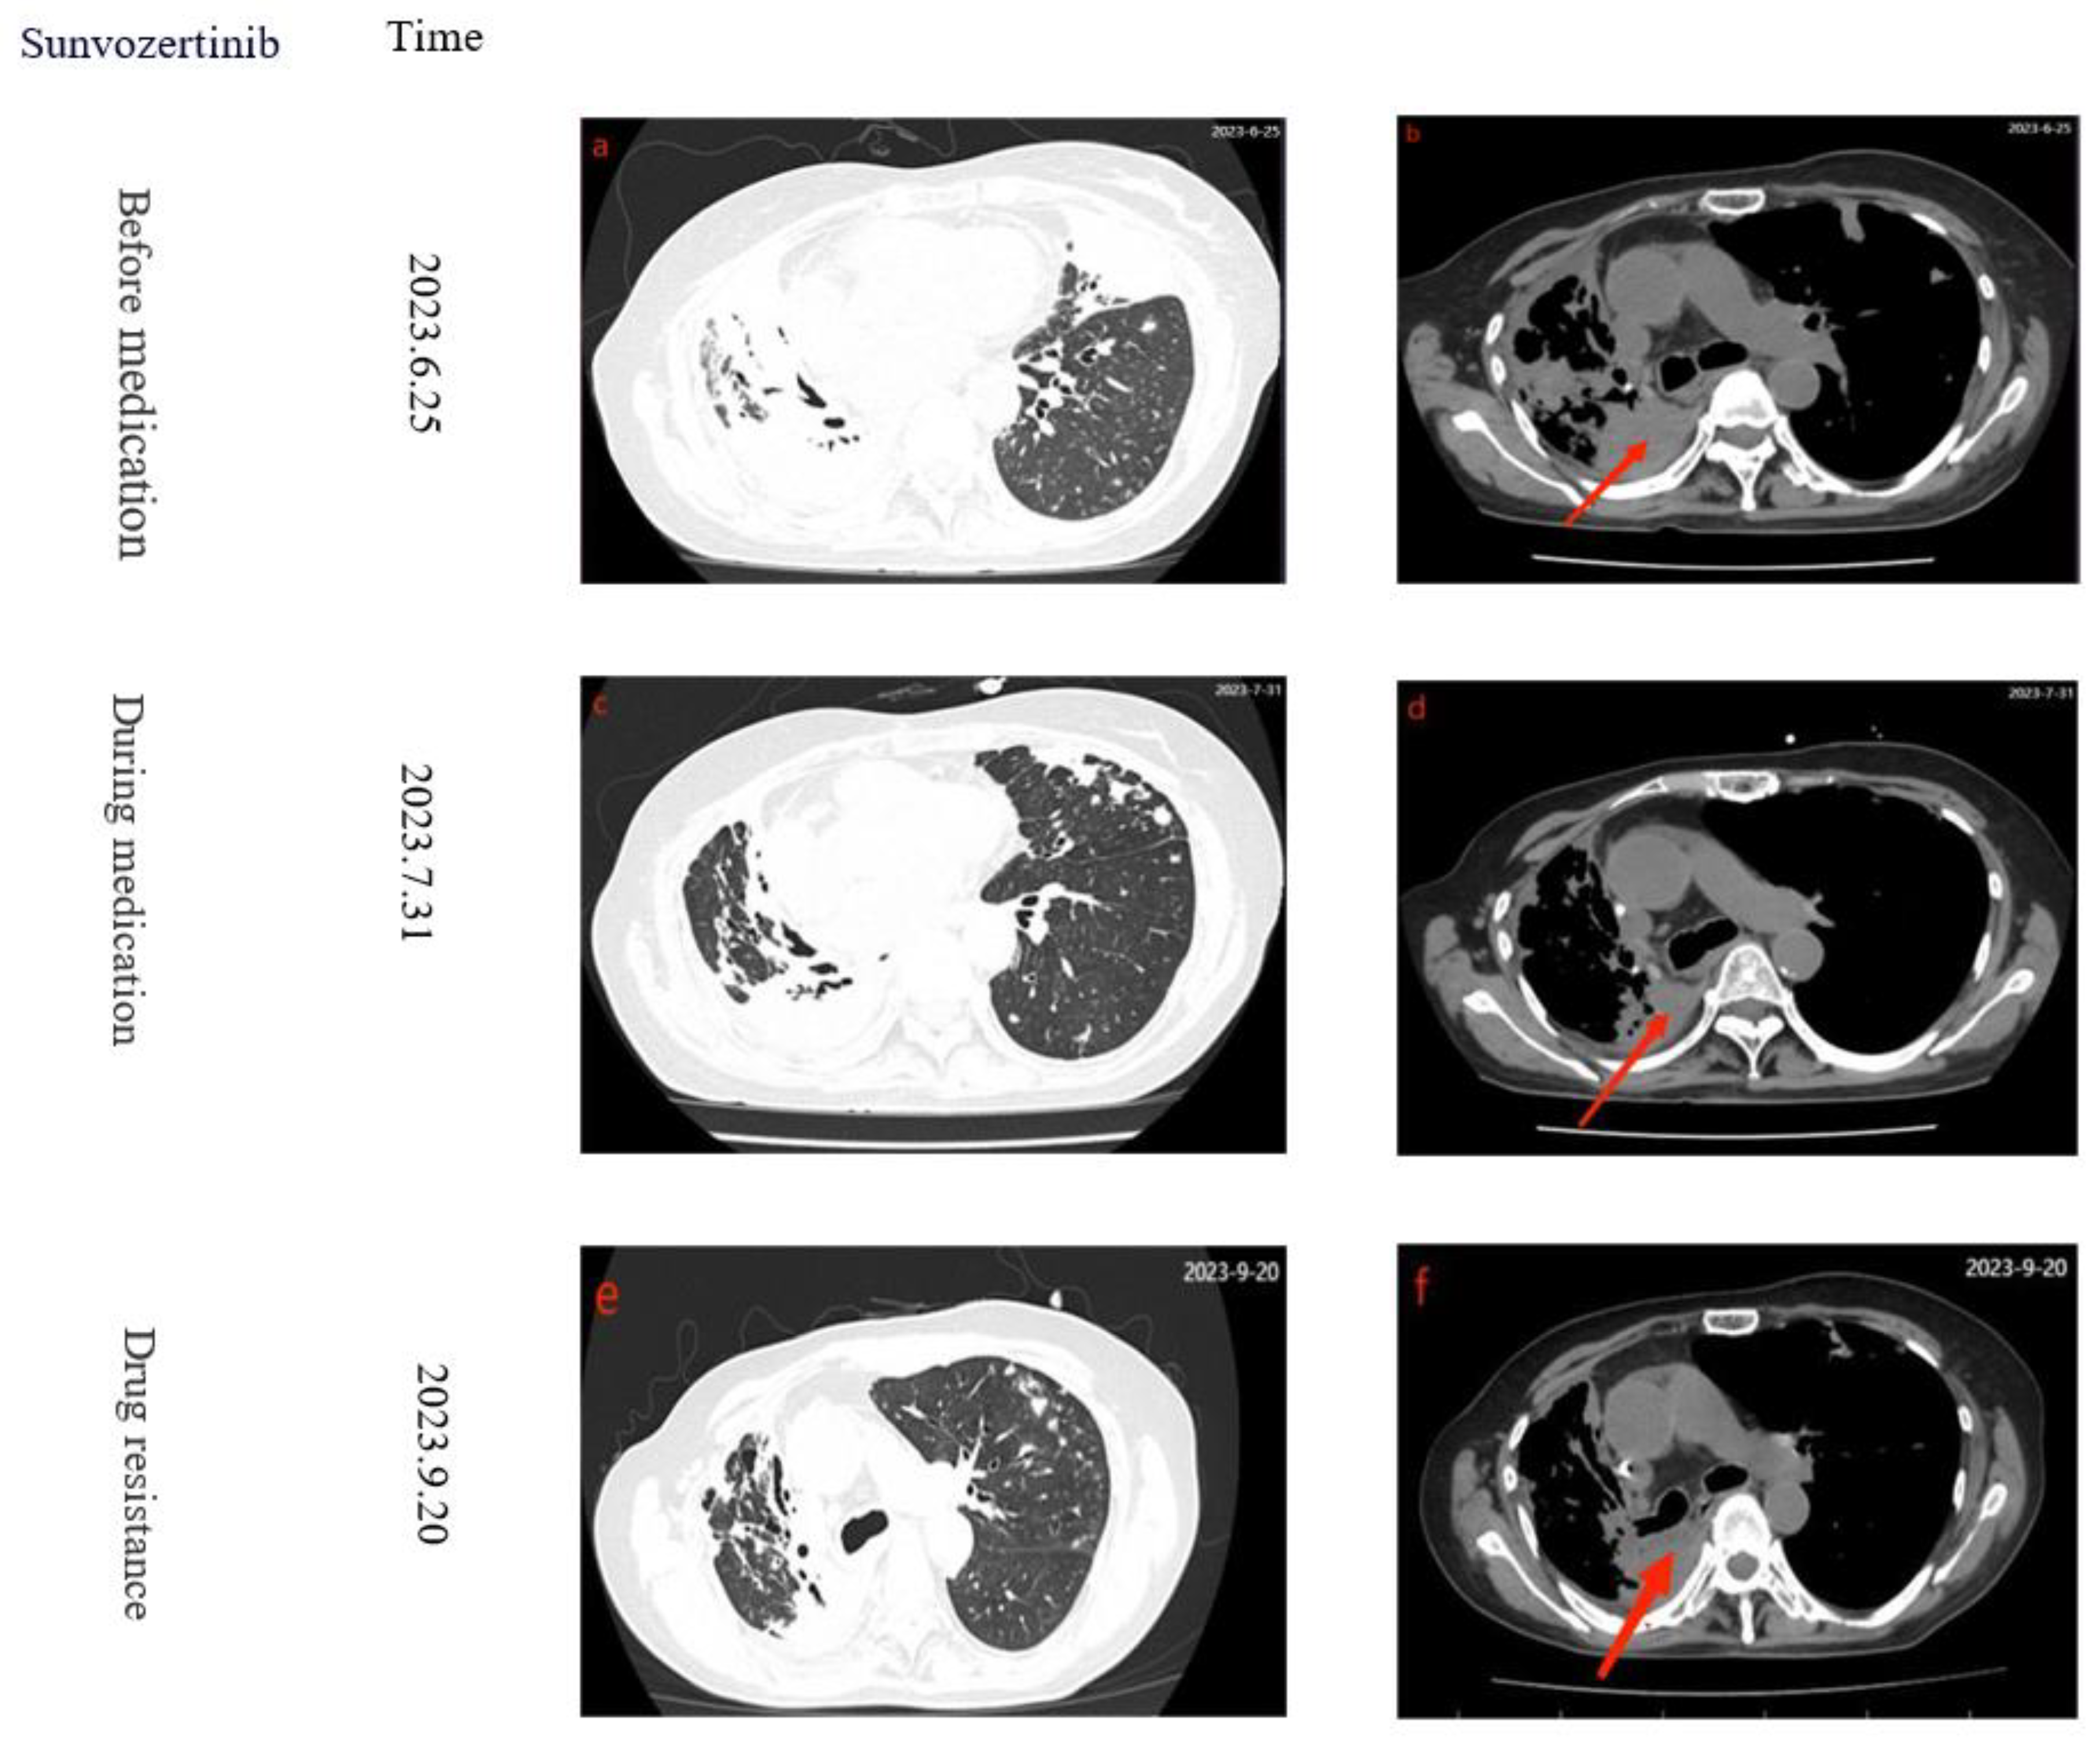

After using Lenvatinib for two months, on June 25, 2023, the patient experienced sudden onset of dyspnea, worsened wheezing, altered consciousness, bedridden and unable to move, with SPO2 94%, BP 162/88mmHg, respiratory rate 22 breaths /min, and white blood cell count of 10.12*109/L. Chest CT showed multiple patchy high-density lesions in both lungs (Figure 2 a-b), indicating resistance to the treatment. Lenvatinib was discontinued and switched to Sunvozertinib 300mg/Qd. After three days of Sunvozertinib, the patient's wheezing and dyspnea improved, mental status became clear, SPO2 99%, BP 129/76mmHg, and respiratory rate was 16 breaths/min. After continuing the treatment for one week, the patient was able to walk and was discharged with continued use of Sunvozertinib. One month later, the patient returned to the hospital for a follow-up examination. The patient had stable breathing and a clear consciousness. A chest CT scan revealed a reduction in the size of the cancerous lesions (Figure 2 c-d). After 50 days, the patient was readmitted due to chest tightness, and CT revealed tumor progression (Figure 2 e-f). After developing resistance to Sunvozertinib, patients discontinued the use of the drug, the PFS with Sunvozertinib was 87 days. After a 17-day cessation of the medication, on October 7, 2023, the patient was admitted to a local hospital for palliative care due to respiratory distress. However, the treatment had limited efficacy, and while on a ventilator, the patient's blood oxygen saturation ranged from 90% to 93%. Eventually, on November 20, the patient died due to respiratory distress. Finally, considering the patient's 16-year history of lung cancer and multiple drug resistances, the patient's family expressed understanding regarding the patient's death .The specific treatment timeline can be seen in (Figure 1)

Figure 2. Serial computed tomography axial sections showing disease development. Red arrows indicate tumor lesions. Treatments and time line are presented to the left of the scans.